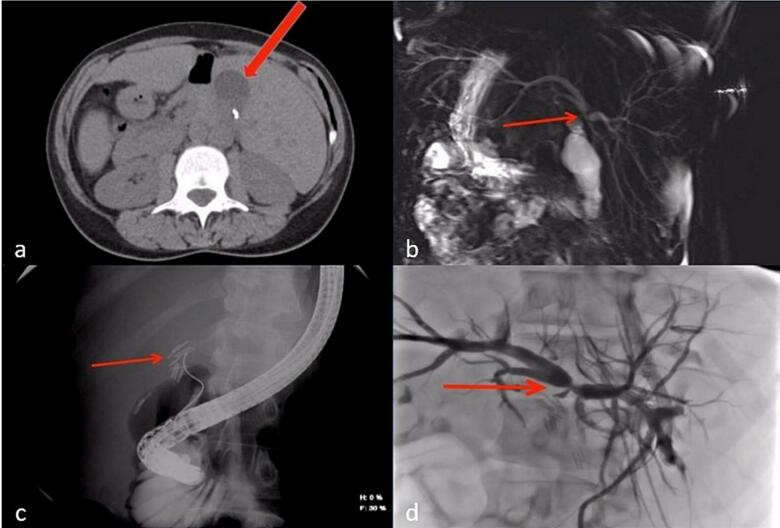

A series of images were obtained as follows:

- A non-contrast CT scan of the abdomen revealed a small perihepatic fluid collection (Fig. 2a).

- Magnetic resonance cholangiopancreatography (MRCP) was obtained, revealing complete occlusion of the common hepatic duct (CHD) just below the bifurcation of the right and left hepatic ducts (Bismuth-Strasberg Type E3 bile duct injury) [ref. 7] (Fig. 2b).

- Endoscopic retrograde cholangiopancreatography (ERCP) was attempted, though cannulating the duct was challenging due to her abnormal anatomy. It showed complete occlusion of the CBD and CHD with multiple clips (Fig. 2c).

- Percutaneous transhepatic cholangiography (PTC) was also performed, revealing biliary tree dilatation with complete occlusion of the CHD just below the bifurcation (Bismuth-Strasberg Type E3 bile duct injury) [ref. 7] with multiple large clips at the occlusion site (Fig. 2d).